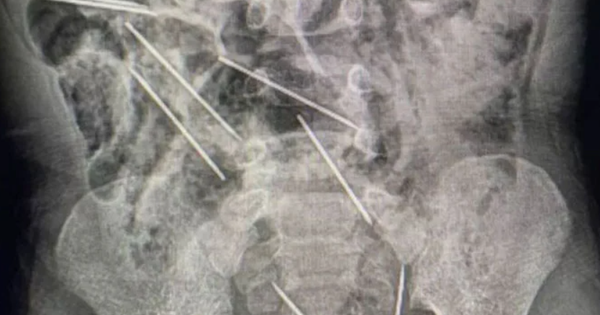

Hình chụp X-quang cho thấy có kim trong vùng bụng của cậu bé - Ảnh: Chính quyền khu vực San Martin

Trong lúc phẫu thuật, các bác sĩ phát hiện những cây kim đã cắm vào các phần khác nhau trong bụng cậu bé, đe dọa nghiêm trọng đến sức khỏe.

"Khi ở trong phòng phẫu thuật và mổ bụng cậu bé ra, chúng tôi thấy nhiều mảnh kim loại và nhận ra chúng là kim", bác sĩ Efrain Salazar tại Bệnh viện II-2 Tarapoto kể.

Ca phẫu thuật kéo dài hai giờ và tất cả tám chiếc kim đều được lấy ra thành công. Đội ngũ y tế đã xử lý những tổn thương nhỏ do kim gây ra ở ruột non của cậu bé.